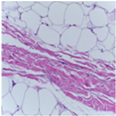

| Image Class | BreakHis Dataset(40×) | |||

| Benign | Malignant | |||

| Original images |  |  |  |  |

| MFF-ClassificationNet heatmaps |  |  |  |  |